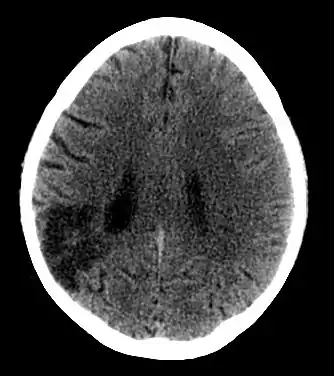

PACI (ang. partial anterior circulation infarct) – częściowy zawał mózgu obejmujący zakres unaczynienia tętnicy przedniej lub środkowej mózgu. Jest to rodzaj zawału mózgu związany z częściową niedrożnością jednej z tętnic krążenia przedniego mózgu (obejmującego tętnicę środkową i tętnicę przednią).